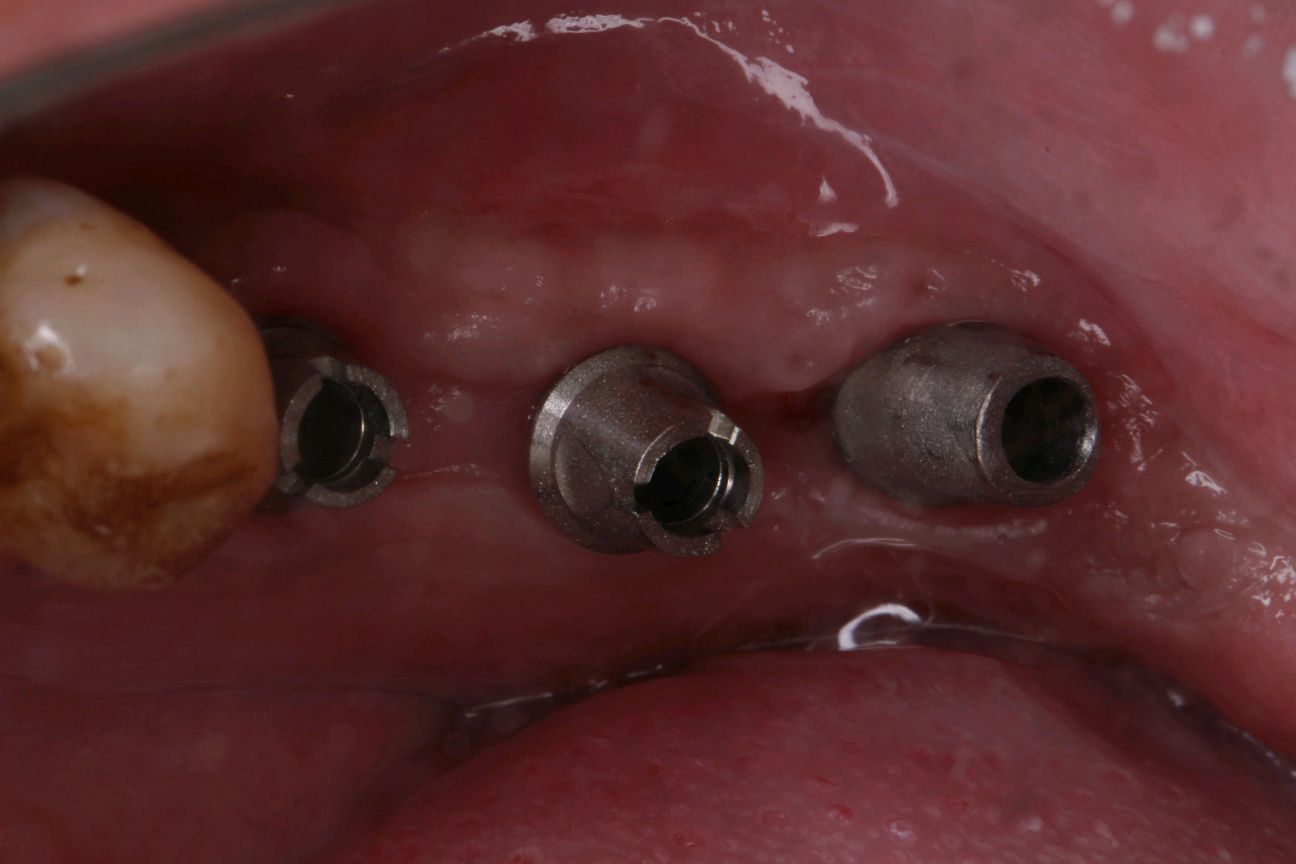

患者自愿选择安卓健种植体。牙槽嵴吸收较多,高度和宽度不足。拔出后植入骨粉骨膜。待骨条件良好后。35植入种植体4.0*10mm;36植入种植体4.6*10mm;37植入种植体4.6*8mm。待骨结合良好后。二期三期如期进行。余近日戴牙。

术后